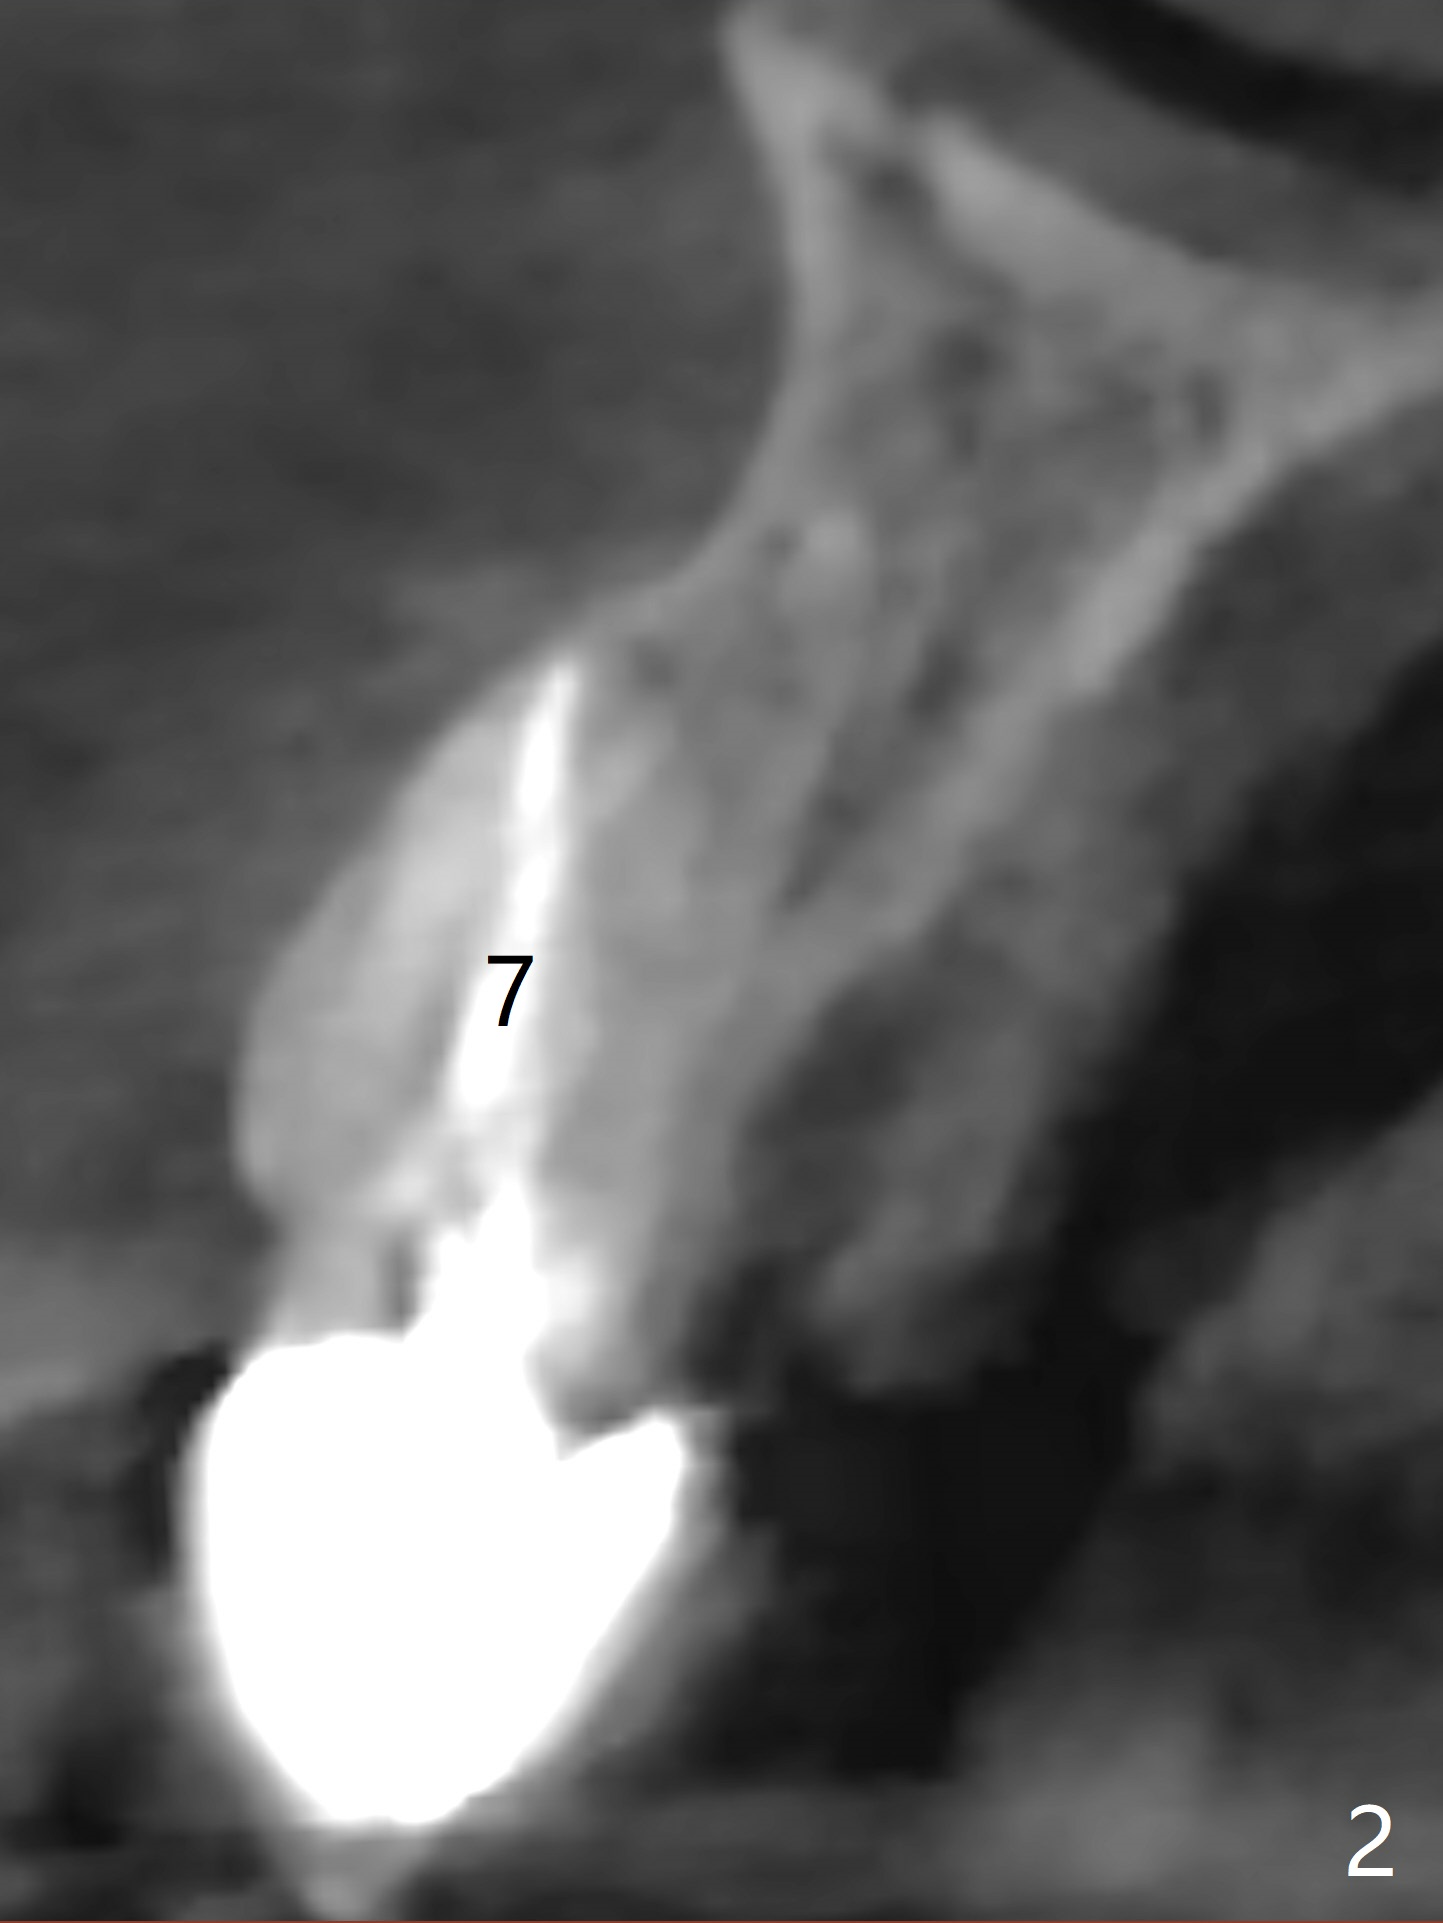

How to Control Trajectory of Immediate Implant Using Guided Surgery?

Two years 2 months post cementation (4.5x12 mm).